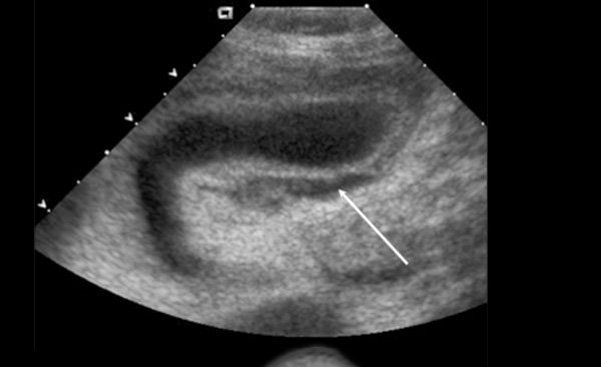

Nhiều nghiên cứu đánh giá kích thước khối máu tụ dịch màng nuôi để tiên lượng mức độ nguy hiểm, khối máu tụ càng to thì tiên lượng càng kém, người ta có nhiều phương pháp đánh giá khối máu tụ như đo kích thước khối máu tụ hoặc tỷ lệ khối máu tụ so với kích thước túi thai hoặc chu vi túi thai...

Nếu đo kích thước khối máu tụ để đánh giá thường không chính xác vì cùng một kích thước khối máu tụ ở tuổi thai khác nhau thì tiên lượng khác nhau. Ví dụ: Tụ máu dưới màng nuôi 20mm ở tuổi thai 6 tuần thì khác hẳn tụ máu dưới màng nuôi thai 11 tuần.

Do đó người ta thường tiên lượng dựa trên tỷ lệ kích thước khối máu tụ và túi thai. Tỷ lệ này càng tăng thì càng tăng tỷ lệ sảy thai

- Kích thước < 10%: Nguy cơ sảy thai 5,8%.

- Kích thước 10 -25%: Nguy cơ sảy thai 8.9%.

- Kích thước 25-50%: Nguy cơ sảy thai 10,8%.

- Kích thước > 50%: Nguy cơ sảy thai 23,3%.